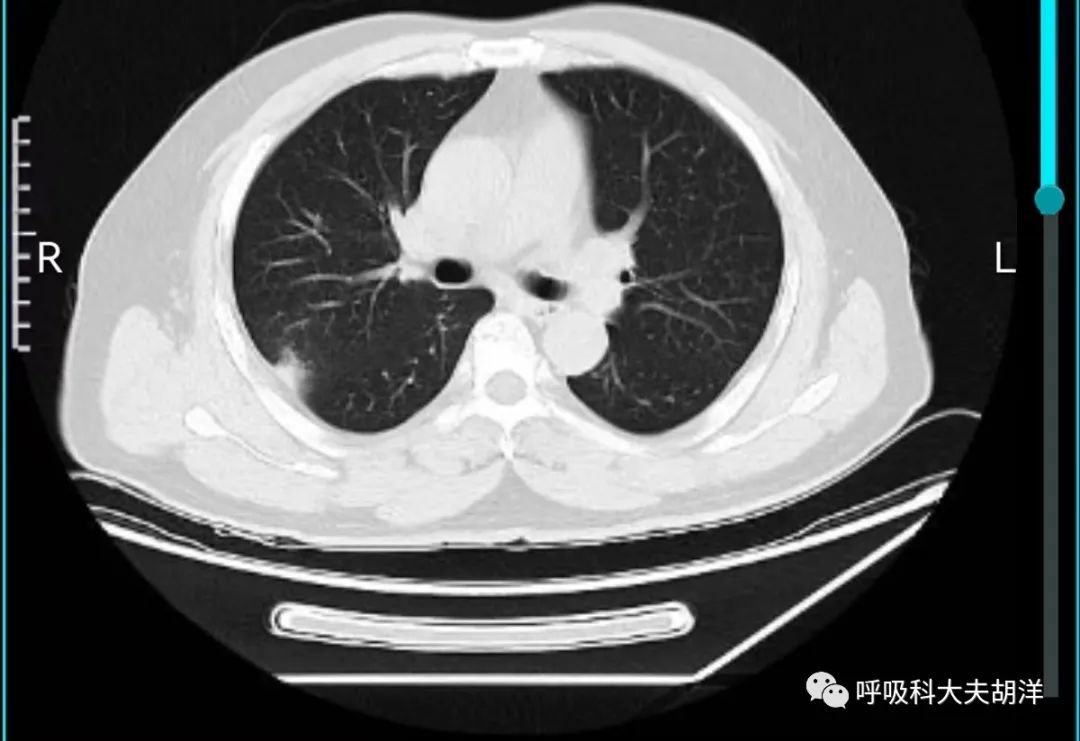

肺结节RADS分级是肺结节分类的一种方式,通常是依据CT下结节的大小、密度、形态学状况、生长速度等,将肺结节分为6个等级。其目的是辅助评估肺结节的良、恶性,或者说判断高危还是低危结节。

3类(未定性结节 恶性概率1-2%)

对于新发或初筛的结节直径大于10毫米,进行CT检查时可能出现模糊或磨玻璃边缘、部分磨玻璃密度、树芽征、卫星灶等特征都归为三类结节。随访2年内稳定的实性结节或者随访时间小于5年内的稳定的亚实性结节,如果结节直径在5-9毫米之间,也归为3类肺结节。处理:一般建议6个月随访复查。